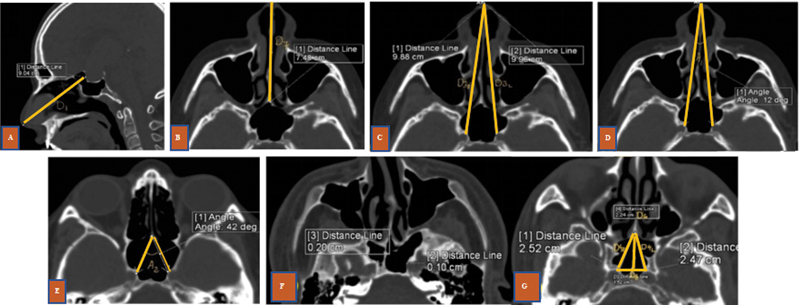

引言 内窥镜经蝶手术(ETS)是垂体手术的标准做法。在 ETS 中,蝶鞍暴露是决定残留疾病的主要因素。关于蝶鞍解剖变异对术中蝶鞍暴露影响的研究文献并不多。目的 本研究旨在确定蝶窦变异是否对蝶窦暴露和残余肿瘤体积有影响。方法 这是一项前瞻性研究,于 2020 年 6 月至 2022 年 6 月期间在印度南部的一家三级医疗中心进行,共有 21 名计划接受 ETS 的研究参与者。评估术前计算机断层扫描(CT)和磁共振成像(MRI)参数与术中蝶窦暴露面积和残余肿瘤体积的关系。结果 蝶窦尺寸,如蝶窦前宽(平均 = 1.89 ± 0.51 厘米)、最大宽度(平均 = 2.94 ± 1.09 厘米)、蝶窦前深(平均 = 1.14 ± 0.55 厘米)、蝶窦上深(平均 = 1.08 ± 0.24 cm)、髌下深度(平均 = 2.36 ± 0.92 cm)、髌前高度(平均 = 2.22 ± 0.47 cm)或 9 个颈内动脉(ICA)相关测量值与术中平均蝶鞍暴露面积(0.57 ± 0.28 cm 2)没有任何相关性。此外,蝶鞍暴露是否充分与残余肿瘤也没有关系。与无残留肿瘤的患者(5.9 [6.8-5.2] cm 3)相比,有残留肿瘤的患者术前肿瘤体积更高(20.2 [55.3-13.2] cm 3)。肿瘤的扩展与残留肿瘤体积有显著关系。结论 根据本研究,蝶窦的解剖变异不会影响蝶窦暴露的充分性。关于残余肿瘤体积以及术前肿瘤体积和扩展情况,还需要进一步研究。

Introduction  Endoscopic transsphenoidal surgery (ETS) is the standard practice in pituitary surgeries. The sellar exposure becomes the main factor which determines the residual disease in ETS. Not many studies can be found in the literature on the influence of anatomical variations of the sphenoid on intraoperative sella exposure. Objective  The aim of the current study is to ascertain whether sphenoid sinus variations play a role in sellar exposure and residual tumor volume. Methods  This is a prospective study conducted in a south Indian tertiary care center between June 2020 to June 2022, with 21 study participants who were scheduled to have ETS. The relation of preoperative computed tomography (CT) and magnetic resonance imaging (MRI) parameters with the intraoperative area of sellar exposure and residual tumor volume was evaluated. Results  Sphenoid sinus dimensions, like presellar width (mean = 1.89 ± 0.51 cm), maximum width (mean = 2.94 ± 1.09 cm), presellar depth (mean = 1.14 ± 0.55 cm), suprasellar depth (mean = 1.08 ± 0.24 cm), infrasellar depth (mean = 2.36 ± 0.92 cm), presellar height (mean = 2.22 ± 0.47 cm), or the 9 internal carotid artery (ICA)-related measures, did not have any correlation with the mean intraoperative area of sellar exposure (0.57 ± 0.28 cm 2 ). Also, the adequacy of sellar exposure did not relate to the residual tumor. Preoperative tumor volume was found to be higher (20.2 [55.3-13.2] cm 3 ) in patients with residual tumor compared with those with no residual tumor (5.9 [6.8-5.2] cm 3 ). Tumor extension had a significant association with the residual tumor volume. Conclusion  According to the present study, anatomical variations of the sphenoid sinus do not influence the adequacy of sellar exposure. Further studies need to be undertaken concerning residual tumor volume as well as preoperative tumor volume and extension.